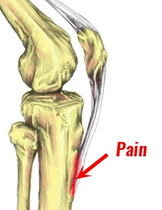

* condition that causes pain and swelling below the knee joint, where the patellar tendon attaches to the top of the shinbone (tibia), a spot called the tibial tuberosity.

*It is a traction apophysitis at the skeletally immature tibial tubercle due to repetitive strain on the secondary ossification center of the tibial tuberosity.

*It can lead to inflammation of the patellar tendon at the tibial tuberosity, resulting in pain and swelling just below the knee.

*Traction apophysitis occurs when repeated excessive load pulls on the tendon insertion causing partial avulsions of the apophysis and inflammation

- Repeated traction apophysitis on the anterior portion of the developing can cause the ossification center to crack

- This can result in callus formation during healing.

- The affected area may become fibrous, creating a separate persistent ossicle, or may show complete bony union with some enlargement of the tibial tuberosity.

- Avulsion fracture of tibial tuberosity may also occur